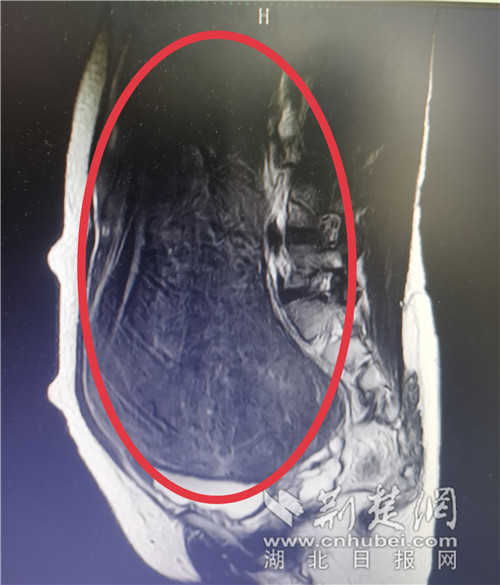

金女士入院后,科室专家为其完善了相关的术前检查,发现瘤体大小超过篮球,上端已接近剑突,下端到达盆腔深处,左右侧达到两侧腹,形状不规则,几乎长满整个肚子,子宫体受挤压发生偏移,输尿管也受挤压造成轻微肾积水。

金女士的子宫肌瘤长满了腹腔与盆腔。通讯员供图